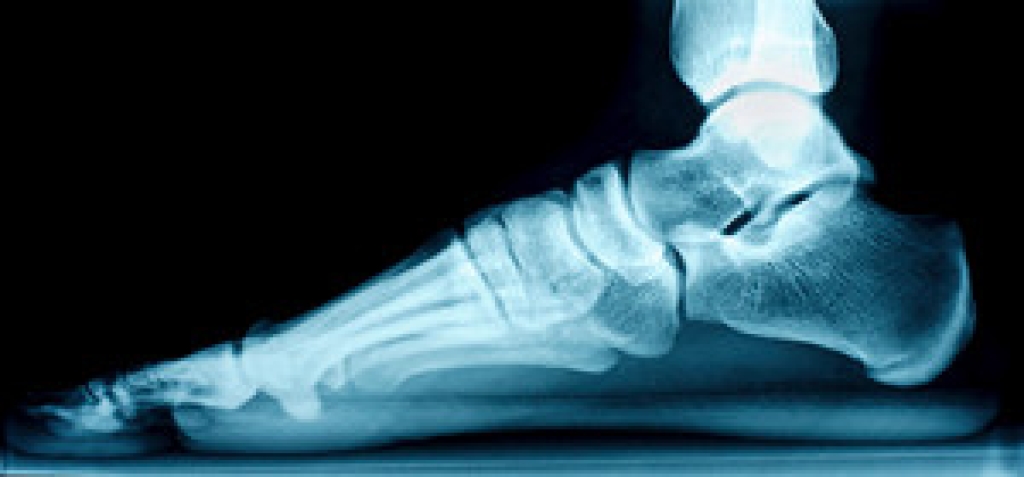

Cracked Heels

It is important to moisturize your cracked heels in order to prevent pain, bleeding, and infection. The reason cracked heels form is because the skin on the foot is too dry to support the immense pressure placed on them. When the foot expands, the dry skin on the foot begins to split.